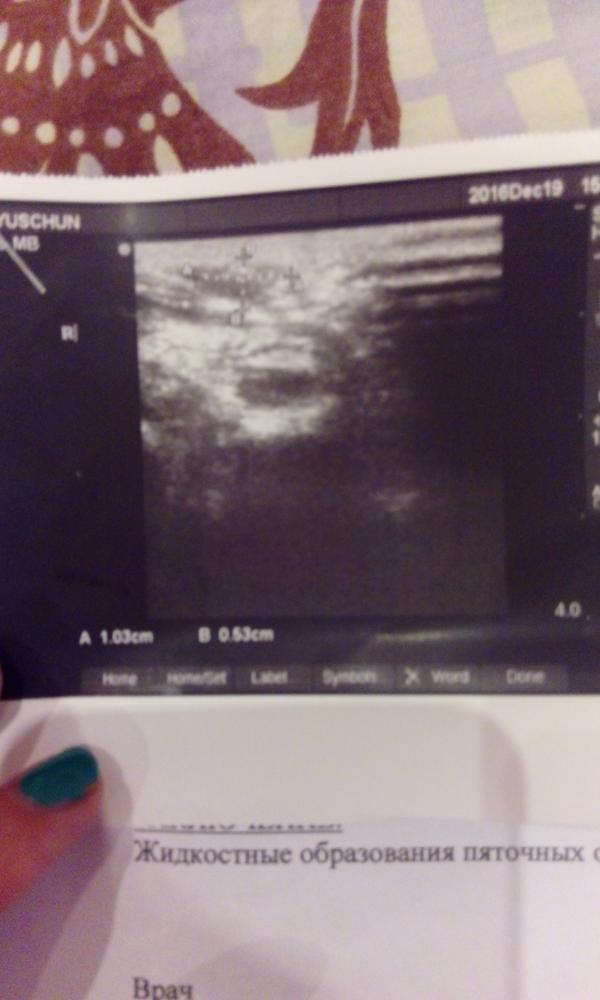

Были мы короче у ортопеда и хирурга.В хирурге я вообще разочаровалась как в специалисте.Она мне долго доказывала,что направление на узи мне не давала😂потом ,когда все же увидела,сказала идти к ортопеду.Говорю вот записались,сейчас пойдем.Попросила зайти после него и рассказать что скажет,мол ей интересно.Ну ок,че.Ортопед когда осматривал,говорит а кто Вас надоумел делать узи,я говорю хирург.Он спросил что хирург сказал,я ему говорю-направил к вам.Он засмеялся😁Ну хоть в одном они сошлись,что долб...